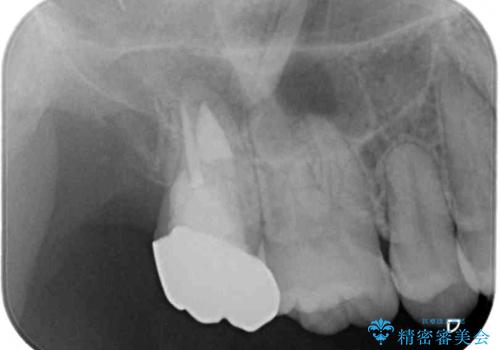

親知らずの抜歯により歯を覆っていた歯肉が切除され、不快感の原因のひとつでもあった歯周ポケットが改善され、奥歯を気にせずに生活できるようになりました。